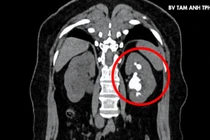

Sỏi san hô kích thước lớn 24×42 mm gây đau lưng dai dẳng, bác sĩ Bệnh viện Đa khoa Tâm Anh TP HCM đã nội soi tán sỏi thận qua đường hầm nhỏ xuyên da lấy sạch sỏi cho người bệnh.